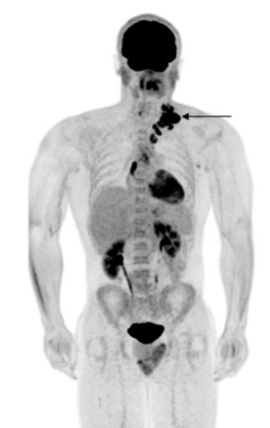

What is the likely source of fever in a patient with the following FDG-PET scan

Approach to fever with Dr. Arikala 12/18/2025